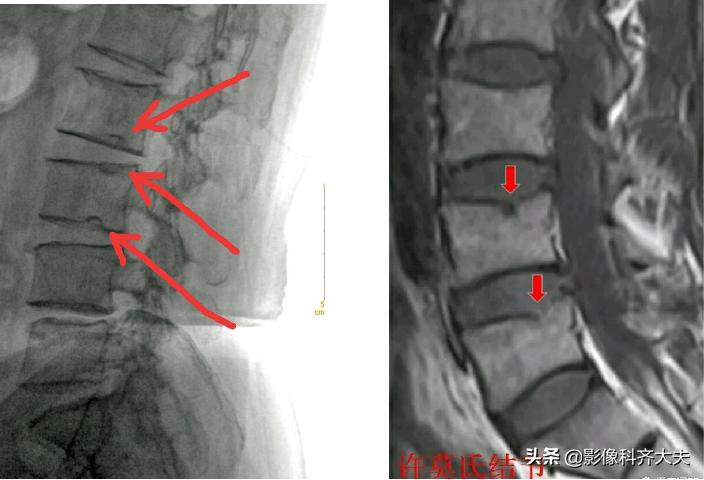

Schmorl结节(许莫氏结节)

Schmorl结节(许莫氏结节),是椎间盘退变时,软骨板变薄及玻璃样变,甚至消失。髓核经软骨板的薄弱或者缺损部疝入椎体内,在椎体内形成软骨结节。

是髓核于椎体上面或者下面形成的圆形或者半圆形的骨质凹陷区,其边缘有硬化。可对称见于相邻两个椎体的上下面,并且可以累及多个椎体。

可以说算是一种特殊类型的椎间盘突出。只不过不像普通椎间盘突出是突出于椎体后缘,而是突出到上下椎体里!

在影像上看,椎体上下缘弧形的凹陷或者骨性透亮区,伴有不同程度的边缘硬化,广泛硬化时椎体呈象牙质样。

Schmorl结节(许莫氏结节)示意图

许莫氏结节并骶管内囊肿